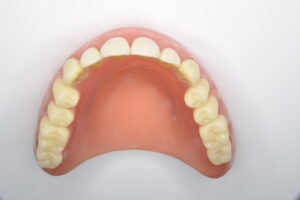

テレスコープ義歯とは──残った歯を守る発想

ここからはテレスコープ義歯の話です。テレスコープ義歯は、クラスプ義歯とは全く逆の発想で作られます。まず歯を加工して金属の「茶筒状のキャップ(内冠)」で包み、その上に外冠と呼ばれる義歯本体を精密に重ね合わせます。装着後は、歯と義歯が一体化するように設計されているのです。

この構造により、噛む力は歯が最も強いとされる上下の歯軸方向にだけ伝わります。硬い食べ物でも力が分散され、歯や歯ぐきに無理なく伝わるため、歯への局所的な負担が小さくなります。着脱も歯軸方向に沿った動きなので、横揺れを生じにくく、歯にかかる力が安定するのです。これが「リジッドサポート(剛性支持)」という考え方です。

さらに、義歯と歯が一体化していることで「噛んだ」という感覚が歯周感覚として脳に伝わりやすくなります。その結果、顎の動きを脳が察知しやすく、歯があったときに近い繊細で自然な咀嚼が可能になります。

まず全顎の虫歯と歯周病の治療を行い、上顎は残存歯すべてに内冠をかぶせて連結し、全体を支えるテレスコープ義歯を製作しました。装着後は「入れ歯」というよりは取り外し可能な長いブリッジの感覚で、違和感がほとんどないとのことです。

このケースは「残った歯をチーム化して守る」発想が有効であった例です。